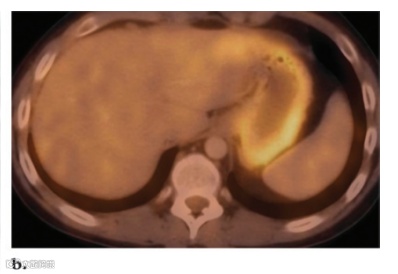

小肠的摄取情况多变,可见时通常为低摄取。结肠摄取程度变异极大,可能非常明显,影响整个或部分结肠。盲肠的摄取通常比结肠其他部分更明显,可能是因为回盲部淋巴组织含量更高(图10)。有时,盲肠的强烈摄取可能使恶性肿瘤或炎症与正常病变的鉴别变得相当困难。PET/CT可以与正常肠道直接进行解剖关联,从而减少诊断的不确定性,从而更准确地解释图像。炎症性肠病儿童可见明显的18F FDG 蓄积。肝脏通常显示均匀的中等摄取,脾脏的摄取相对较弱。

通常,在造血骨髓中可发现强度低于肝脏活性的轻度活性。强度高于肝脏活性的骨髓活性被认为是异常的。正常蓄积通常是均匀的,在儿童中的分布比在成人中更广泛。化疗后可见骨髓活性增加,通常在1个月内消退。贫血引起的增生和造血刺激也可见摄取增加。用造血细胞因子 [如粒细胞集落刺激因子(CSF)、造血生长因子或红细胞生成素] 治疗也会产生弥漫性骨骼FDG蓄积(图16)。在停止粒细胞CSF治疗后,活性增加可持续长达3周;因此,建议将FDG PET推迟到治疗后约4周。此外,在CSF治疗期间,脾脏中可观察到FDG摄取量弥漫性增加,同时骨髓摄取量增加,反映出CSF诱导的脾脏髓外造血(图16)。重要的是要认识到,脾脏活动增加也可能发生在脾外感染患者中;因此,脾脏摄取不应自动解释为脾脏感染或肿瘤。

脾脏是免疫系统的重要组成部分,并且具有多种功能,包括清除荚膜细菌、吞噬作用以及产生炎症物质和免疫球蛋白抗体。据推测,脾脏活动的广泛增强反映了脾外感染时该器官的葡萄糖消耗增加。外部放射治疗几个月后,可以观察到骨髓FDG摄取减少。这种现象归因于脂肪组织取代骨髓。通常,正常骨骼中不会发现FDG摄取。然而,骨骼未成熟的儿科患者可能在骨骺和骨突中出现生理线性摄取(图17)。